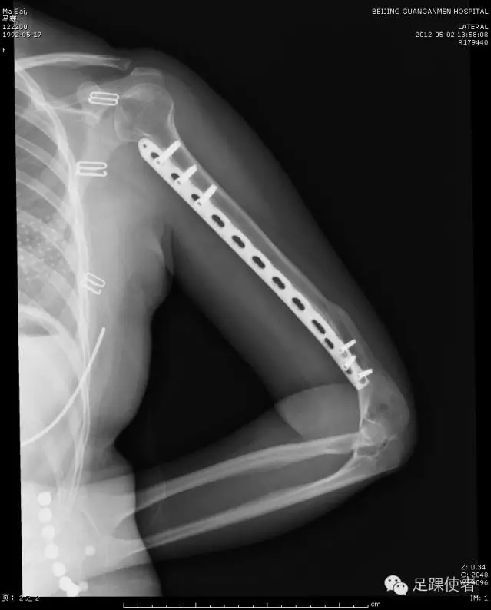

现在我们开展了微创治疗肱骨干骨折的新方法,只需经过两个小切口就可以复位骨折,并且放入一枚很长的钢板。即可靠地固定了骨折,又减小了组织损伤。

目前这种术式在我院已开展百余例,术后效果均良好,患者对疗效也表示满意。